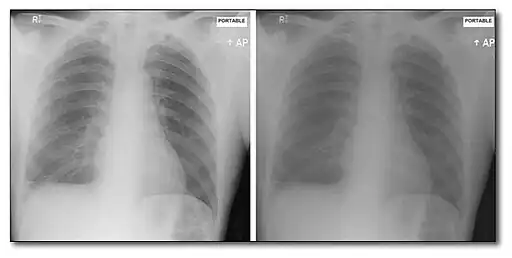

- The important point to appreciate here is that CR images present data which is a superior record of the radiation exposure pattern incident on the cassette. They do not contain regions of over- and/or under-exposure, as is common is film/screen radiography. An improved ability to discriminate within regions of high (or indeed low) transmission results, so that, for example, a renal calculus can be readily depicted within a contrast filled renal pelvis in an IVP. Note that the dynamic range of CR is rather broad and that contrast enhancement techniques are typically applied in a post-processing mode to window through the image data so that particular features of interest can be discerned. Example CR images are shown below: